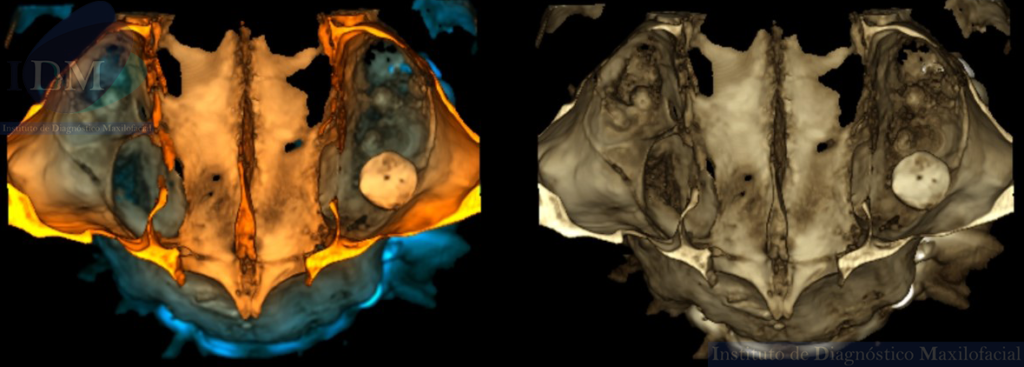

A la evaluación de la tomografía computarizada de haz cónico (TCHC) en los cortes axiales, transaxiales y en la reconstrucción 3D se observa una estructura ovalada hiperdensa heterogénea con contenidos mixtos irregulares localizada en piso del seno maxilar izquierdo con extensión hacia el antro sinusal. Además, en las imágenes tangenciales se observa la presencia de un antrolito adyacente a nivel de la pieza 26.

RECONSTRUCCIÓN 3D